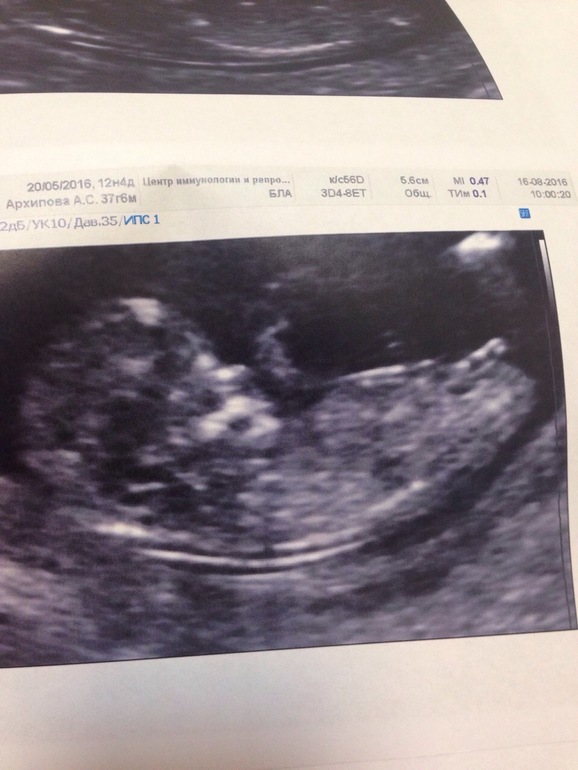

Наш первый скрининг и интрига месяца раскрыта😂😂😂❤️❤️❤️

УЗИ, КТГ, доплерПрошли мы сегодня наш первый скрининг, все у нас ттттт отлично, все риски низкие, малыш совершенно здоровый.

Ну и у нас будет

Замечательная, здоровая, спокойная ДОЧЕНЬКА💞💞💞